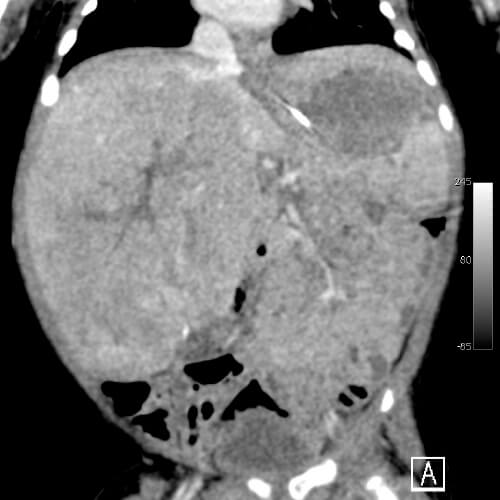

小児外科は心臓外科・脳外科・整形外科分野を除いた小児の一般外科であり、幅広い解剖学的知識が要求される診療科です。また、数100グラムの極低出生体重児から成人並の体重の中学生まで幅広い体格の子供を対象とするため、手術は繊細で正確な操作が要求される難しい科でもあります。当院においても既に、胸腔鏡下肺葉切除や胸腔鏡下縦隔腫瘍切除、腹腔鏡下後腹膜腫瘍切除、腹腔鏡下噴門形成、腹腔鏡下胆嚢摘出、腹腔鏡下先天性胆道拡張症手術、腹腔鏡下脾臓摘出、先天性食道閉鎖症や胎便性腹膜炎、小腸閉鎖症、横隔膜ヘルニア、鎖肛などの新生児手術、壊死性腸炎などの超低出生時体重児手術、胆道閉鎖症に対する葛西手術、ヒルシュスプルング病手術、肝芽腫や神経芽腫、横紋筋肉腫などの腫瘍全摘術、膵頭部腫瘍に対する膵頭十二指腸切除、正中頚嚢胞や側頚瘻などの頚部疾患手術、膵損傷治療など新生児から中学生までの高度な治療の実績が積まれています。

教授(特任)の金子健一朗は先天性胆道拡張症/膵・胆管合流異常の専門家であり、2017年Lancet誌に総説が記載されました(金子業績1. Lancet Gastroenterol Hepatol 2017; 2: 610–18)。